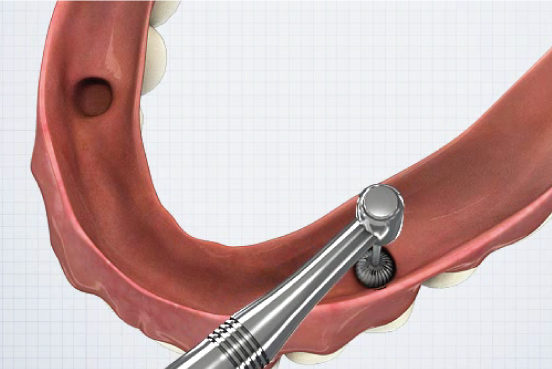

②

- EZ LOCK 전용드라이버를 이용하여 EZ LOCK 체결 (25N~)▼

②

- EZ LOCK 전용드라이버를 이용하여 EZ LOCK 체결 (25N~)▼